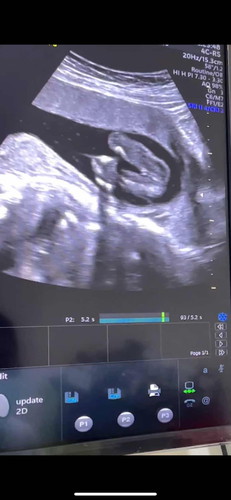

เบื้องต้นหมอบอกว่าเป็นผู้หญิง แต่ยังไม่แน่ชัด เพราะอายุครรภ์พึ่ง18วีค แม่ๆคิดว่าไงคะ